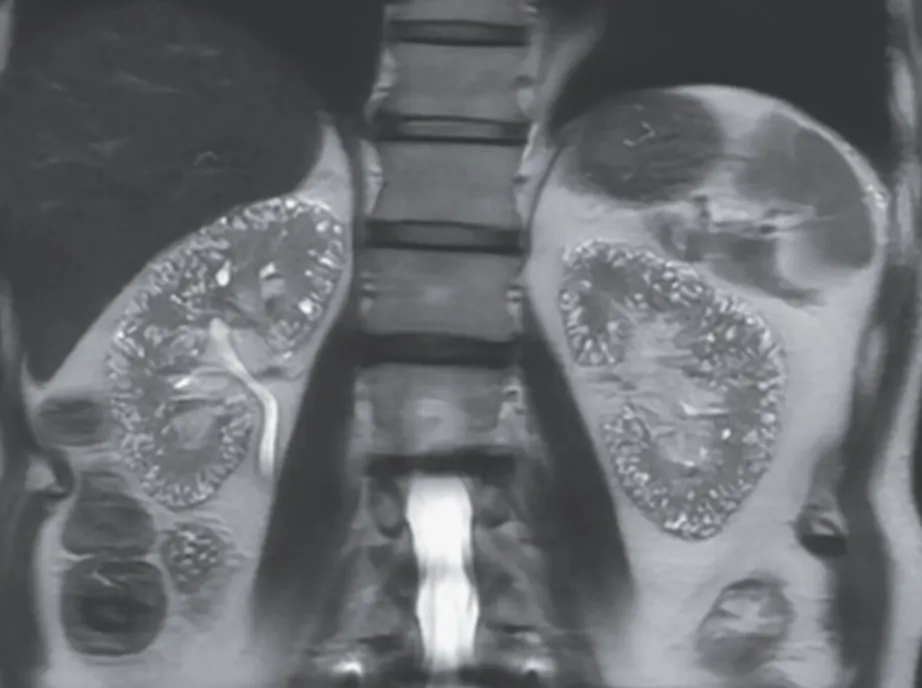

DRC indeterminada ou você esqueceu de fazer o básico? Veja tudo aqui

DRC indeterminada ou você esqueceu de fazer o básico? Veja tudo aqui

DRC “indeterminada” raramente é falta de diagnóstico — quase sempre é falta de método. Tempo de evolução, urina bem avaliada, USG renal e história clínica dirigida mudam conduta e evitam erros comuns na prática nefrológica.